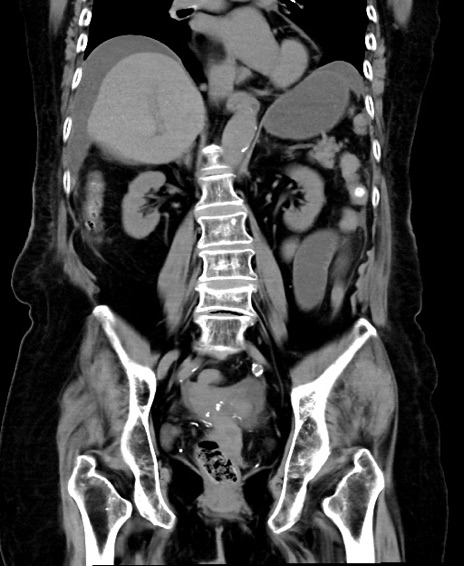

症例40(冠状断像)他院1日前

冠状断像